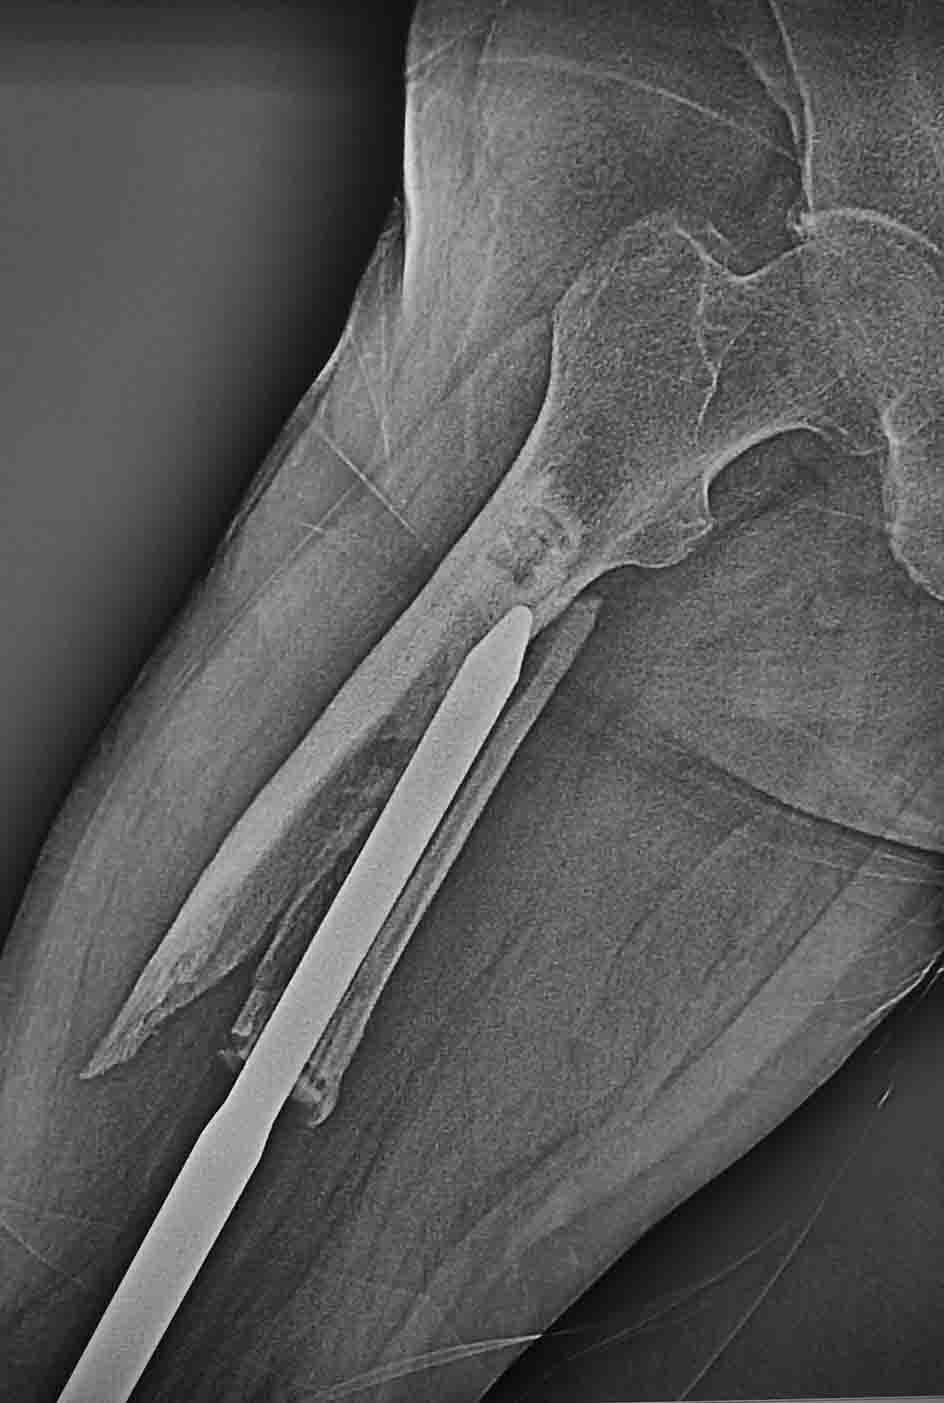

Госпитализирован пациент с перипротезным переломом бедра. Оперирован около 5 лет назад - онкопротез коленного сустава.

Какие возможны варианты лечения, куда можно его ориентировать? Есть ли у него шансы сохранить ногу? Спасибо.